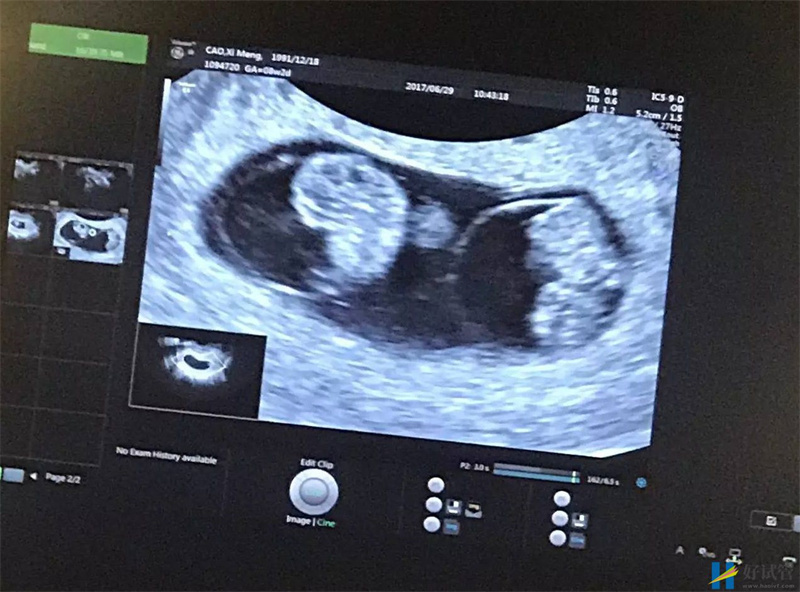

两个胎心:孕期四个月左右,孕妈可以到医院做胎心的监测。如果是怀上了双胞胎,那么就可以监测出两个不同频率的胎心。